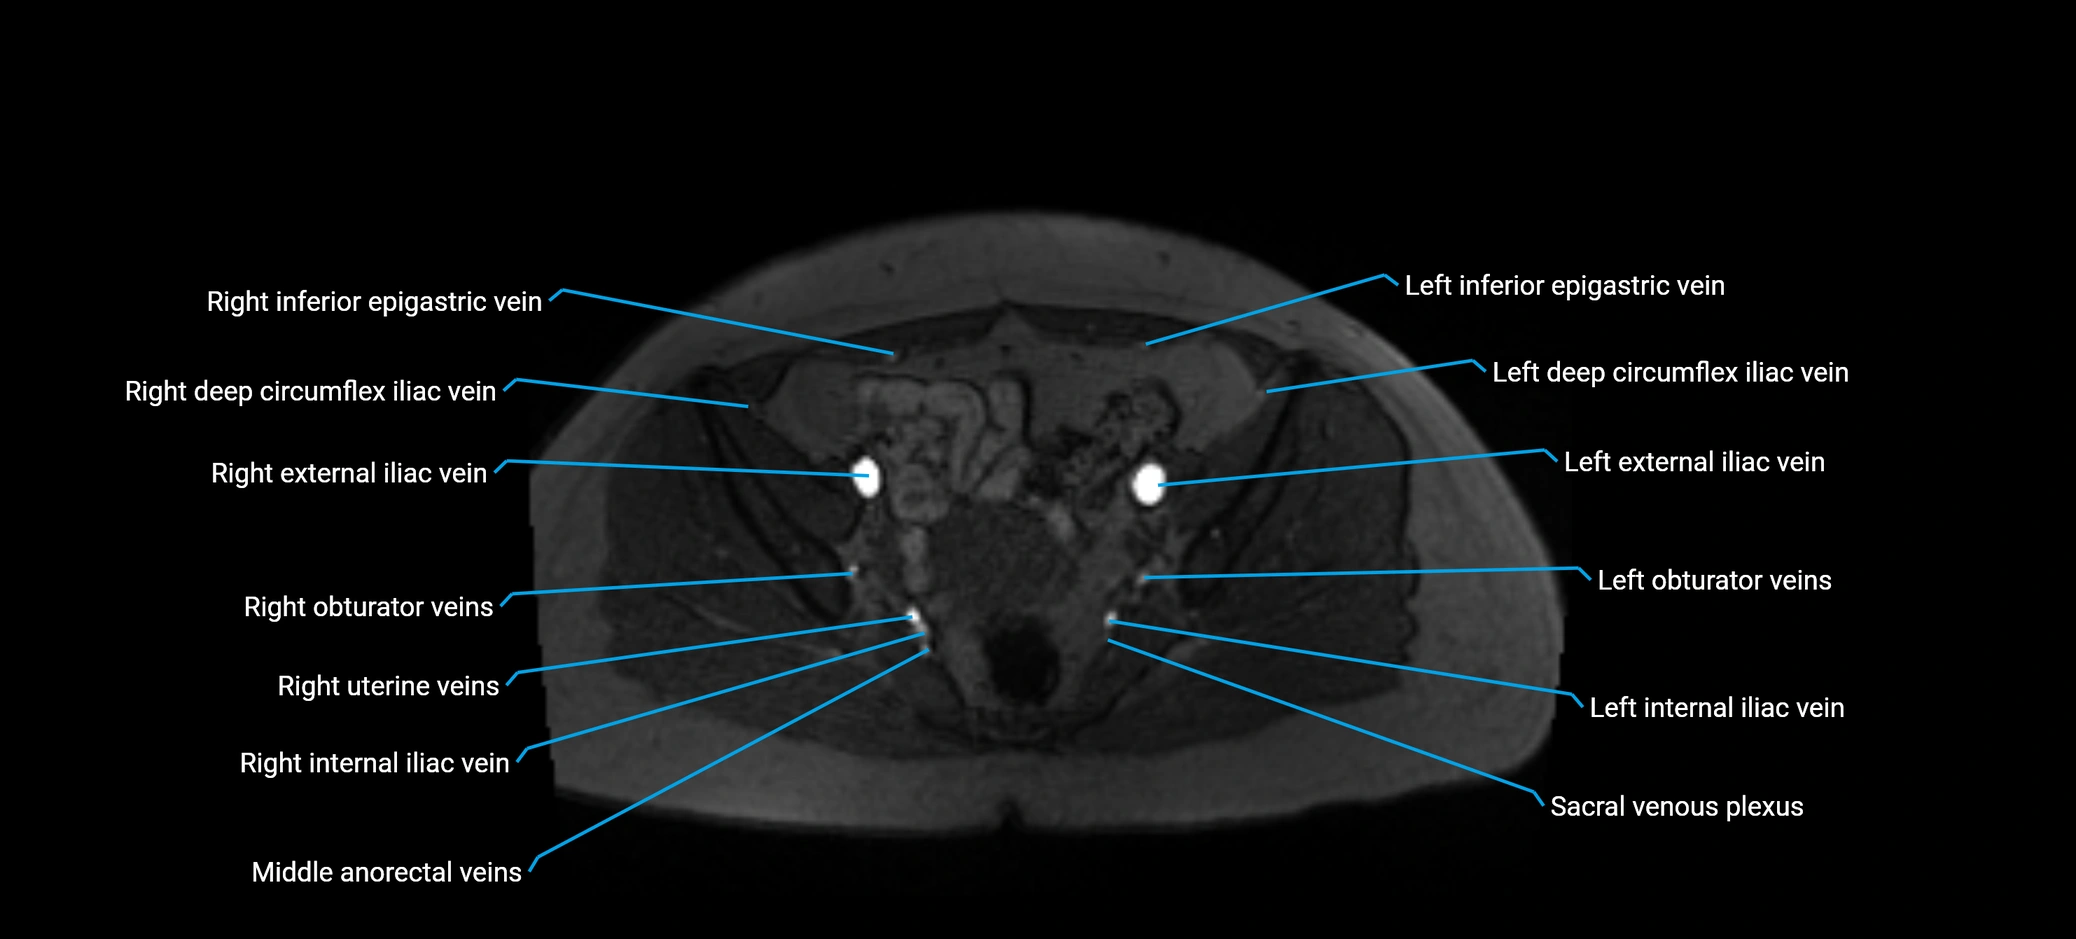

MRI image

image